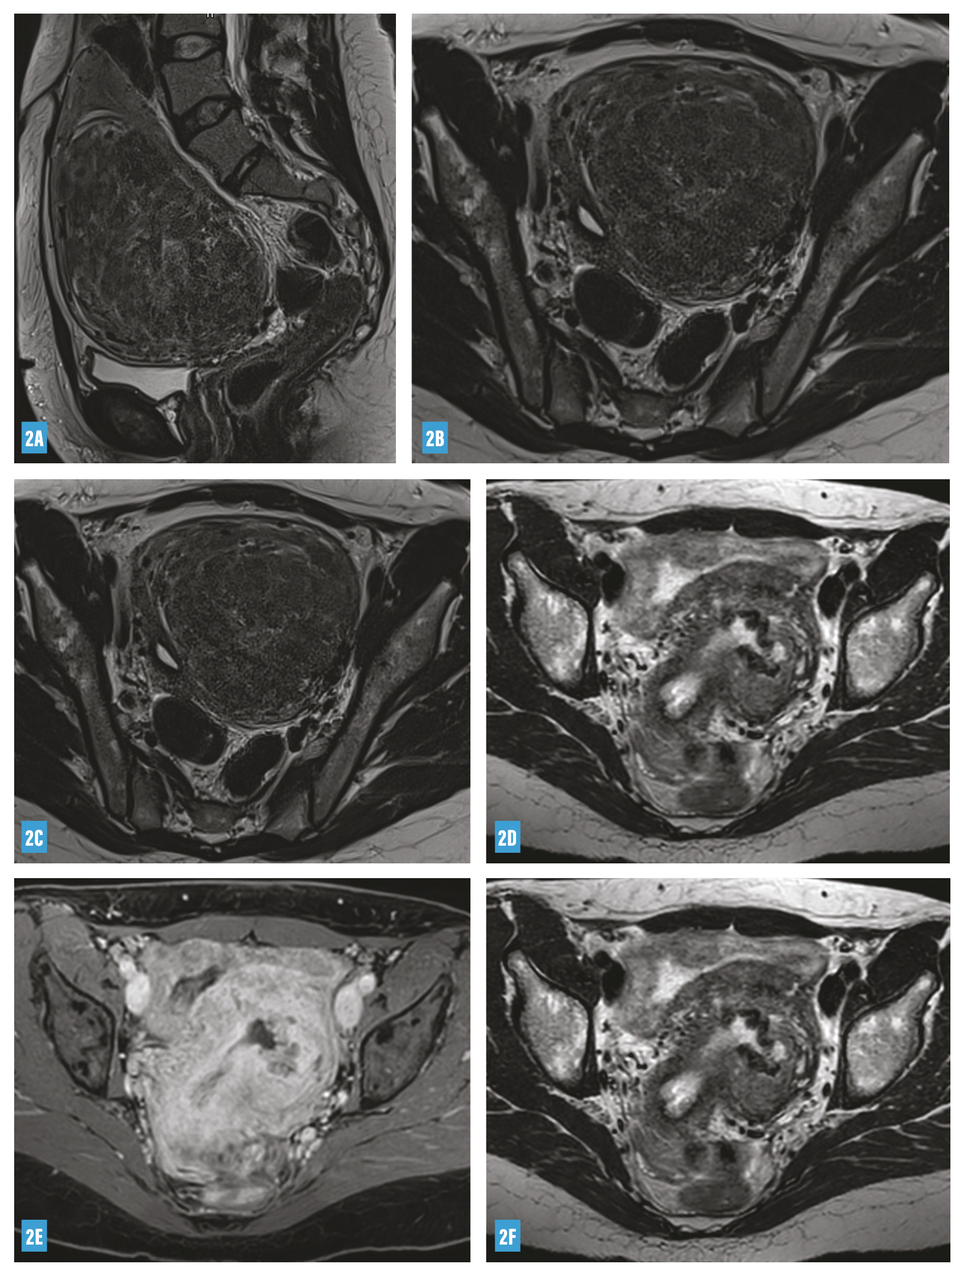

Les possibilités thérapeutiques sont nombreuses pour les myomes de type 3 et plus ; leur efficacité varie de 85 % (myomectomie, embolisation) à 100 % (hystérectomie), avec un taux de complications proportionnel à la radicalité du geste (fig. 2) ; cependant, il est difficile de privilégier un traitement plutôt qu’un autre pour une situation clinique donnée.